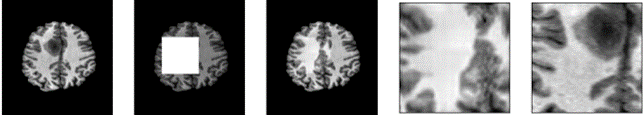

As shown in figure 2, one can see how the problem definition changed according to the amount of data masked. For smaller window sizes, the inpainting network is only required to reconstruct a handful of pixels. However, with larger masks the network is required to reconstruct texture and structure. Additionally, due to adversarial training, the network produces reconstructions without blur.

Figure 5 illustrates snapshots of the sliding window process. The inpainting network restores the masked region to what a normal brain would look like in that area. The inpainting network is naive and does not reconstruct the tumour when partially covered, due to computing L1 loss globally rather than just on the local masked region.